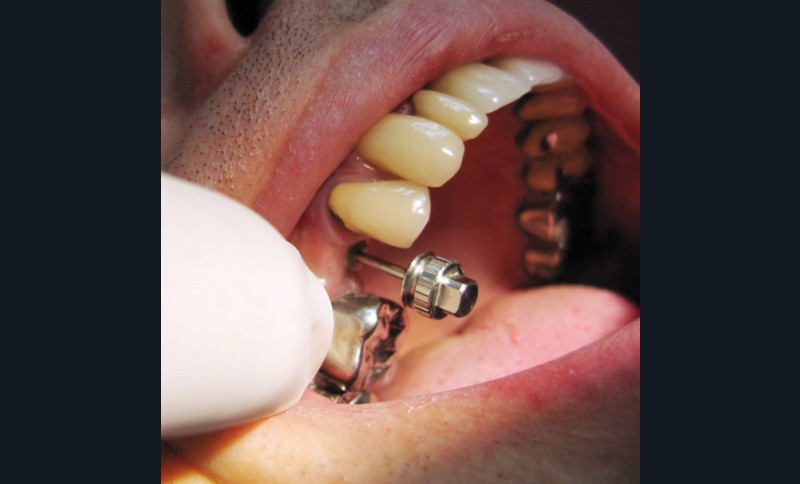

Dépose de la vis de cicatrisation (fig. 4) : l’assistante présente au praticien l’embout du tournevis adapté à la tête de vis de cicatrisation (fig. 5).

Puis le tournevis est calé sur l’embout (fig. 6) et la vis est retirée (fig. 7).